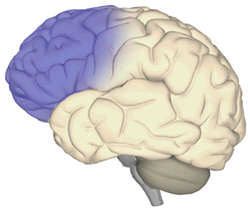

The frontal lobe (shown here in blue) regulates higher “executive” functions of the brain, such as conscious thought, memory, intelligence, concentration, behavior, and personality. Injury to the frontal lobe can result in aggression in some patients.

The frontal lobe (shown here in blue) regulates higher “executive” functions of the brain, such as conscious thought, memory, intelligence, concentration, behavior, and personality. Injury to the frontal lobe can result in aggression in some patients.

“In summary, aggression following TBI is associated with multiple biological and psychosocial factors, including major depression, substance abuse, and impaired social function as well as the presence of brain injury involving the frontal lobe. These findings suggest that interventions aimed at treating major depression or substance abuse and improving social function may help reduce episodes of aggression in patients who have suffered traumatic brain injury.”

- Patients with aggressive behavior were more likely to have injuries to the frontal lobe. While non-aggressive patients were more likely to have diffuse brain injuries.